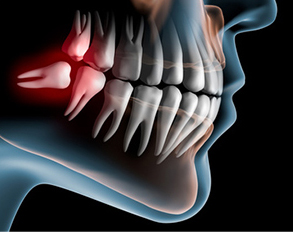

「口腔外科」とは文字通り、口腔(お口の中)の外科処置を行う科目です。歯科医院では、虫歯や歯周病の治療だけでなく、お口の中の様々な疾患に対応しています。「歯は痛くないけれど、口の中に違和感がある」「親知らずが気になる」「顎が開かない」という方は、ご相談ください。